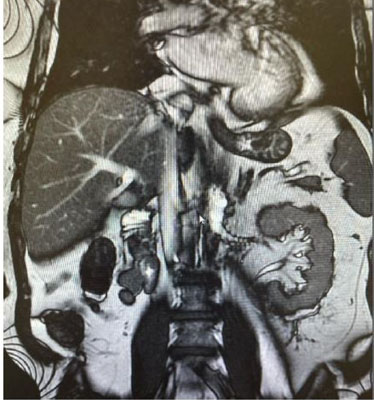

A 58-years-old Saudi male presented with two years history of right painless scrotal mass. There was no history of fever, genital trauma, genital infection, or tuberculosis (TB). The patient denied having nausea, vomiting, diarrhea, flushing, palpitations, or weight changes. On physical examination, the scrotum revealed a right-sided non-tender mass with 2 cm above and not attached to right testis. The left side of the scrotum was normal and no palpable lymph nodes. Normal tumor markers of testicular tumor. Ultrasonography revealed a well-defined, homogeneous, hyperechoic lesion measuring approximately 2 cm in the right extratesticular region.. It was seen superior to right testis and right epididymis and separable from them with high vascularity by Doppler study. Both testes appeared average in size and normal vascularity (Figure 1). Magnetic resonance imaging (MRI) with intravenous (IV) gadolinium contrast for abdominal and pelvis showed right extratesticular soft tissue mass not separable from the spermatic cord and there was no distant metastasis (Figure 2A, Figure 2B, Figure 2C). Based on images, provisional clinical diagnosis of a benign paratesticular mass was made and the patient underwent exploratory excision of the mass with preservation of cord and testis. The patient was discharged two days after surgery. Histopathology showed grossly a single soft gray light brown tissue mass measuring 2×2 cm with white firm focally fleshy cut surface. Microscopically, cells arranged in nested and trabecular growth pattern. The neoplasm is composed of tumor nests comprising of round cells with abundant granular eosinophilic-basophilic focally clear cytoplasm surrounded by sustentacular cells embedded in vascular rich stroma. The lesion exhibited no evidence of capsular invasion, lymphovascular invasion, a diffuse pattern, tumor necrosis, atypical mitosis, or increased mitotic activity. Histopathology reported this mass is paraganglioma.

Figure 2: (A–C) MRI showed right extratesticular soft tissue mass not separable from the spermatic cord.